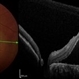

- multicolor

Heidelberg Spectralis - Description

- Multi-color fundus of a 30 yo female with PAMM OD.